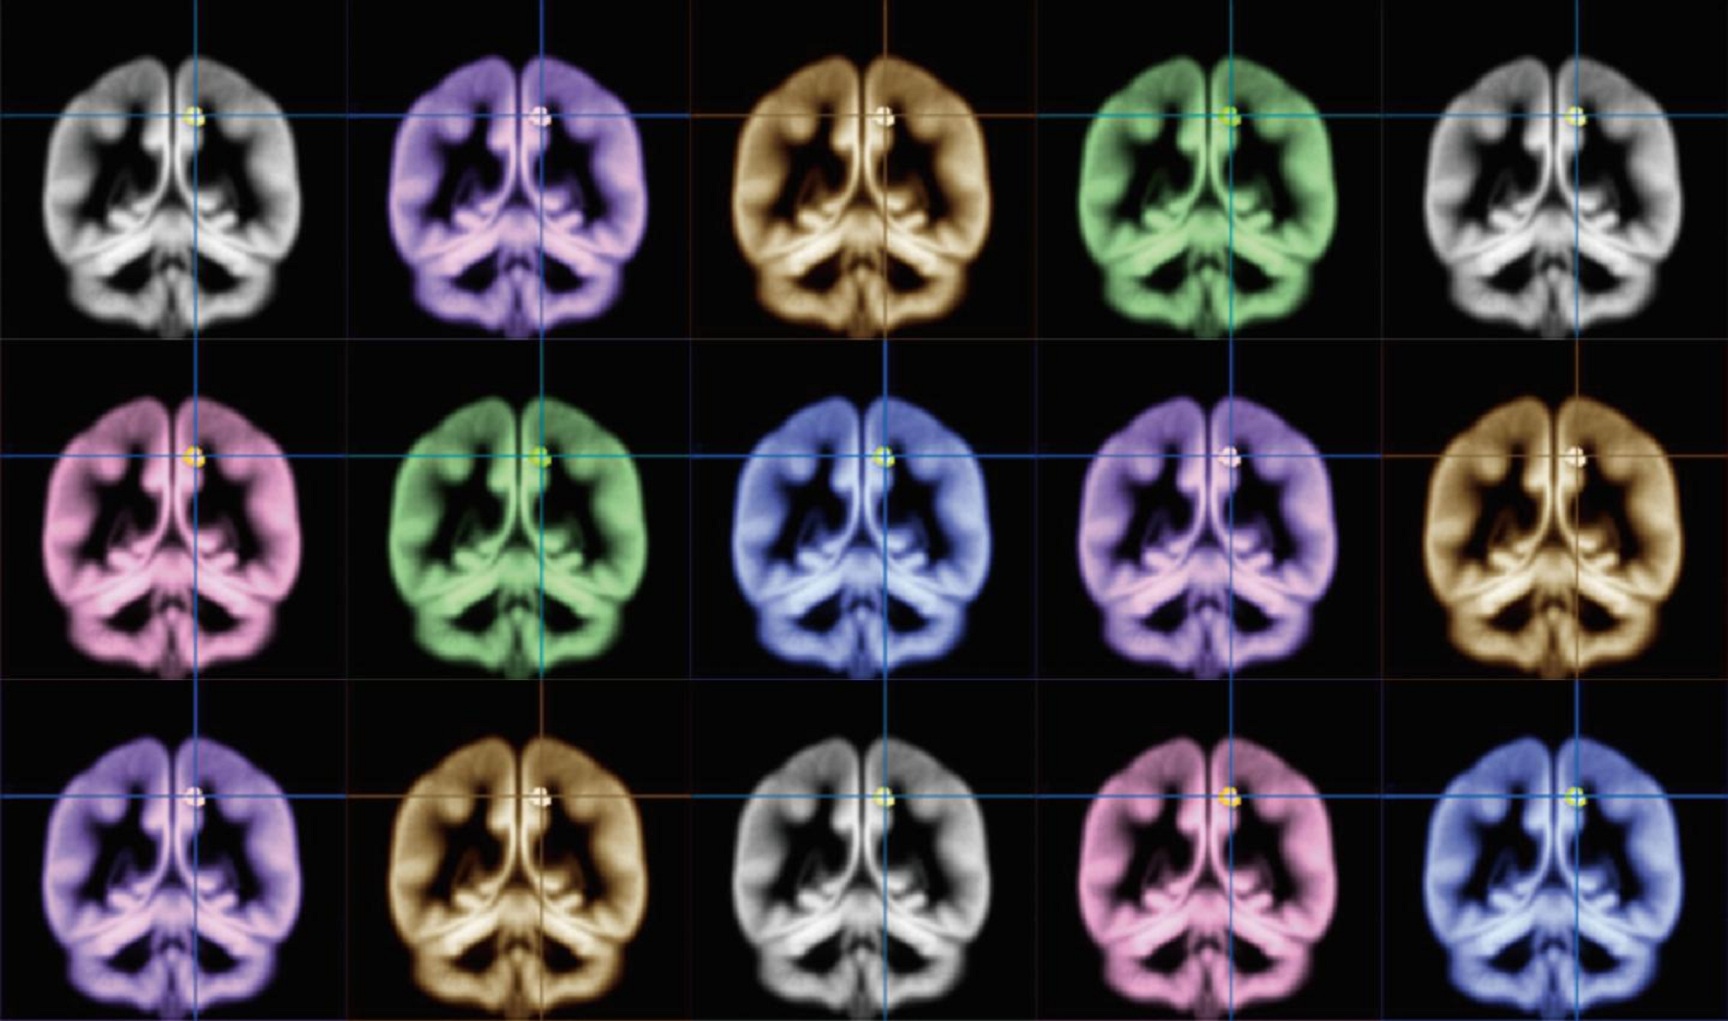

Científicos de la Universidad de Kioto usaron escáneres de imágenes de resonancia magnética para encontrar la localización de la felicidad en el cerebro. Fuente: Universidad de Kioto/Eurekalert!

Por eso, el científico y sus colaboradores se dispusieron a entender las claves del “cerebro feliz”. Para ello escanearon los cerebros de un grupo de voluntarios, usando resonancias magnéticas. También se hizo a los participantes en el estudio una encuesta sobre su nivel de felicidad, el grado de intensidad con que sentían sus emociones, y el nivel de satisfacción vital que tenían.